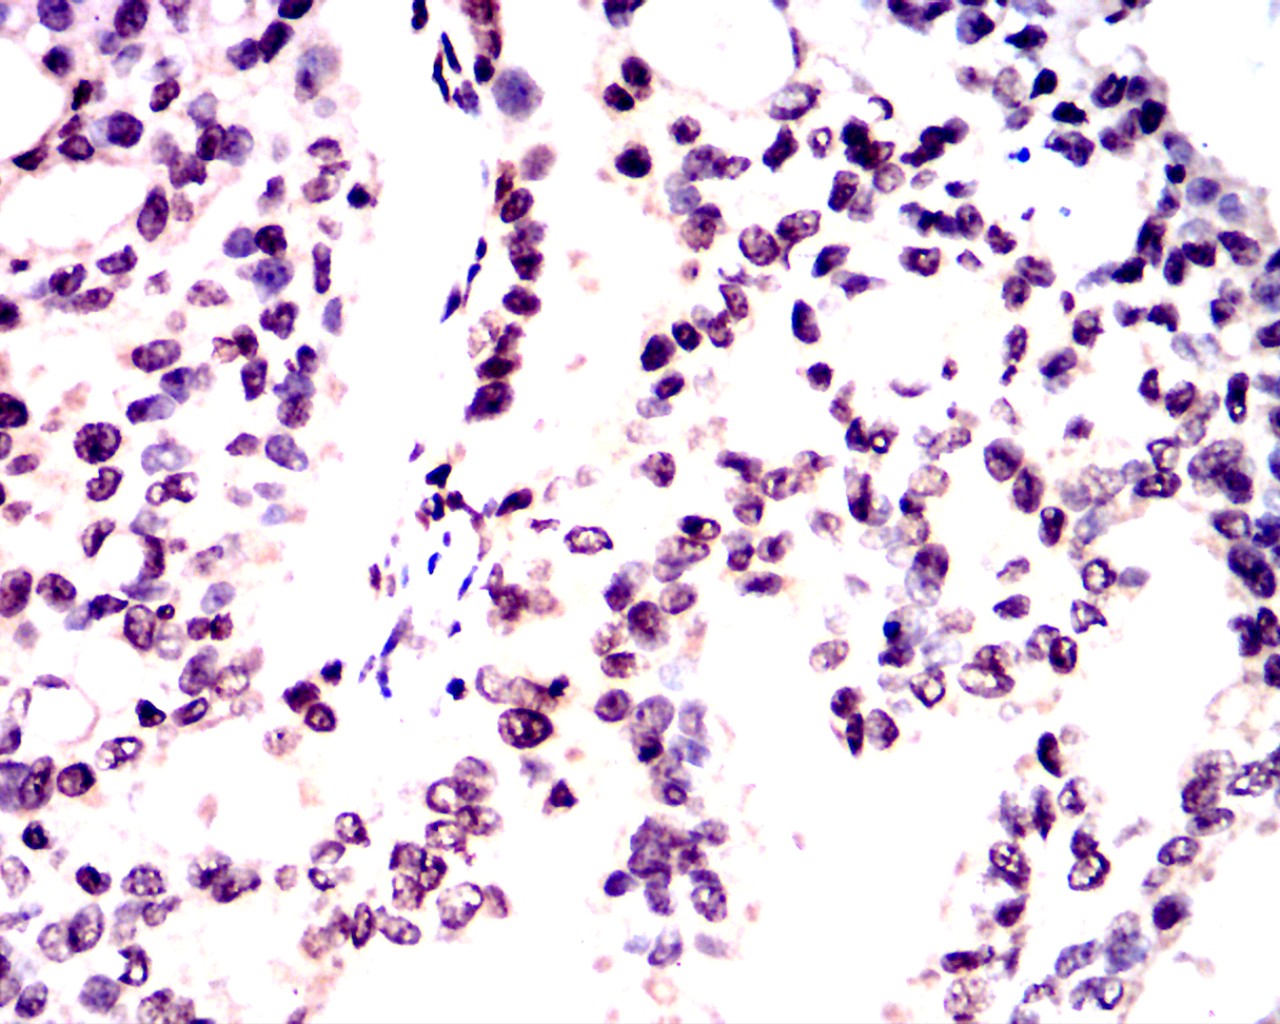

Immunohistochemical analysis of paraffin-embedded thyroid carcinoma tissues using NeuN antibody with DAB staining.Pre-treat the sections with heat-mediated antigen retrieval using sodium citrate buffer (pH 6.0) (OM750020) for 2 minutes. Wash the sections with ddH₂O and PBS (OM750003). Block the tissue with 10% non-immune goat serum(OM760028) at room temperature for 30 minutes. Incubate the tissue with the primary antibody diluted at a ratio of 1:1500 at 4°C overnight. At room temperature, dilute the secondary antibody, Goat Anti-Mouse IgG (H&L) - HRP(OM644366), at a ratio of 1:200 and incubate for one hour. Use DAB(OM760029)as the chromogenic agent. Counterstain the tissue with hematoxylin, and mount the tissue sections with neutral gum.| Product Name | Goat Anti-Mouse IgG (H&L) - HRP |

Immunohistochemical analysis of paraffin-embedded thyroid carcinoma tissues using NeuN antibody with DAB staining.Pre-treat the sections with heat-mediated antigen retrieval using sodium citrate buffer (pH 6.0) (OM750020) for 2 minutes. Wash the sections with ddH₂O and PBS (OM750003). Block the tissue with 10% non-immune goat serum(OM760028) at room temperature for 30 minutes. Incubate the tissue with the primary antibody diluted at a ratio of 1:1500 at 4°C overnight. At room temperature, dilute the secondary antibody, Goat Anti-Mouse IgG (H&L) - HRP(OM644366), at a ratio of 1:200 and incubate for one hour. Use DAB(OM760029)as the chromogenic agent. Counterstain the tissue with hematoxylin, and mount the tissue sections with neutral gum.| Application Notes | WB:1:5000-1:20000 IHC:1:500-1:1000 ICC:1:500-1:1000 |